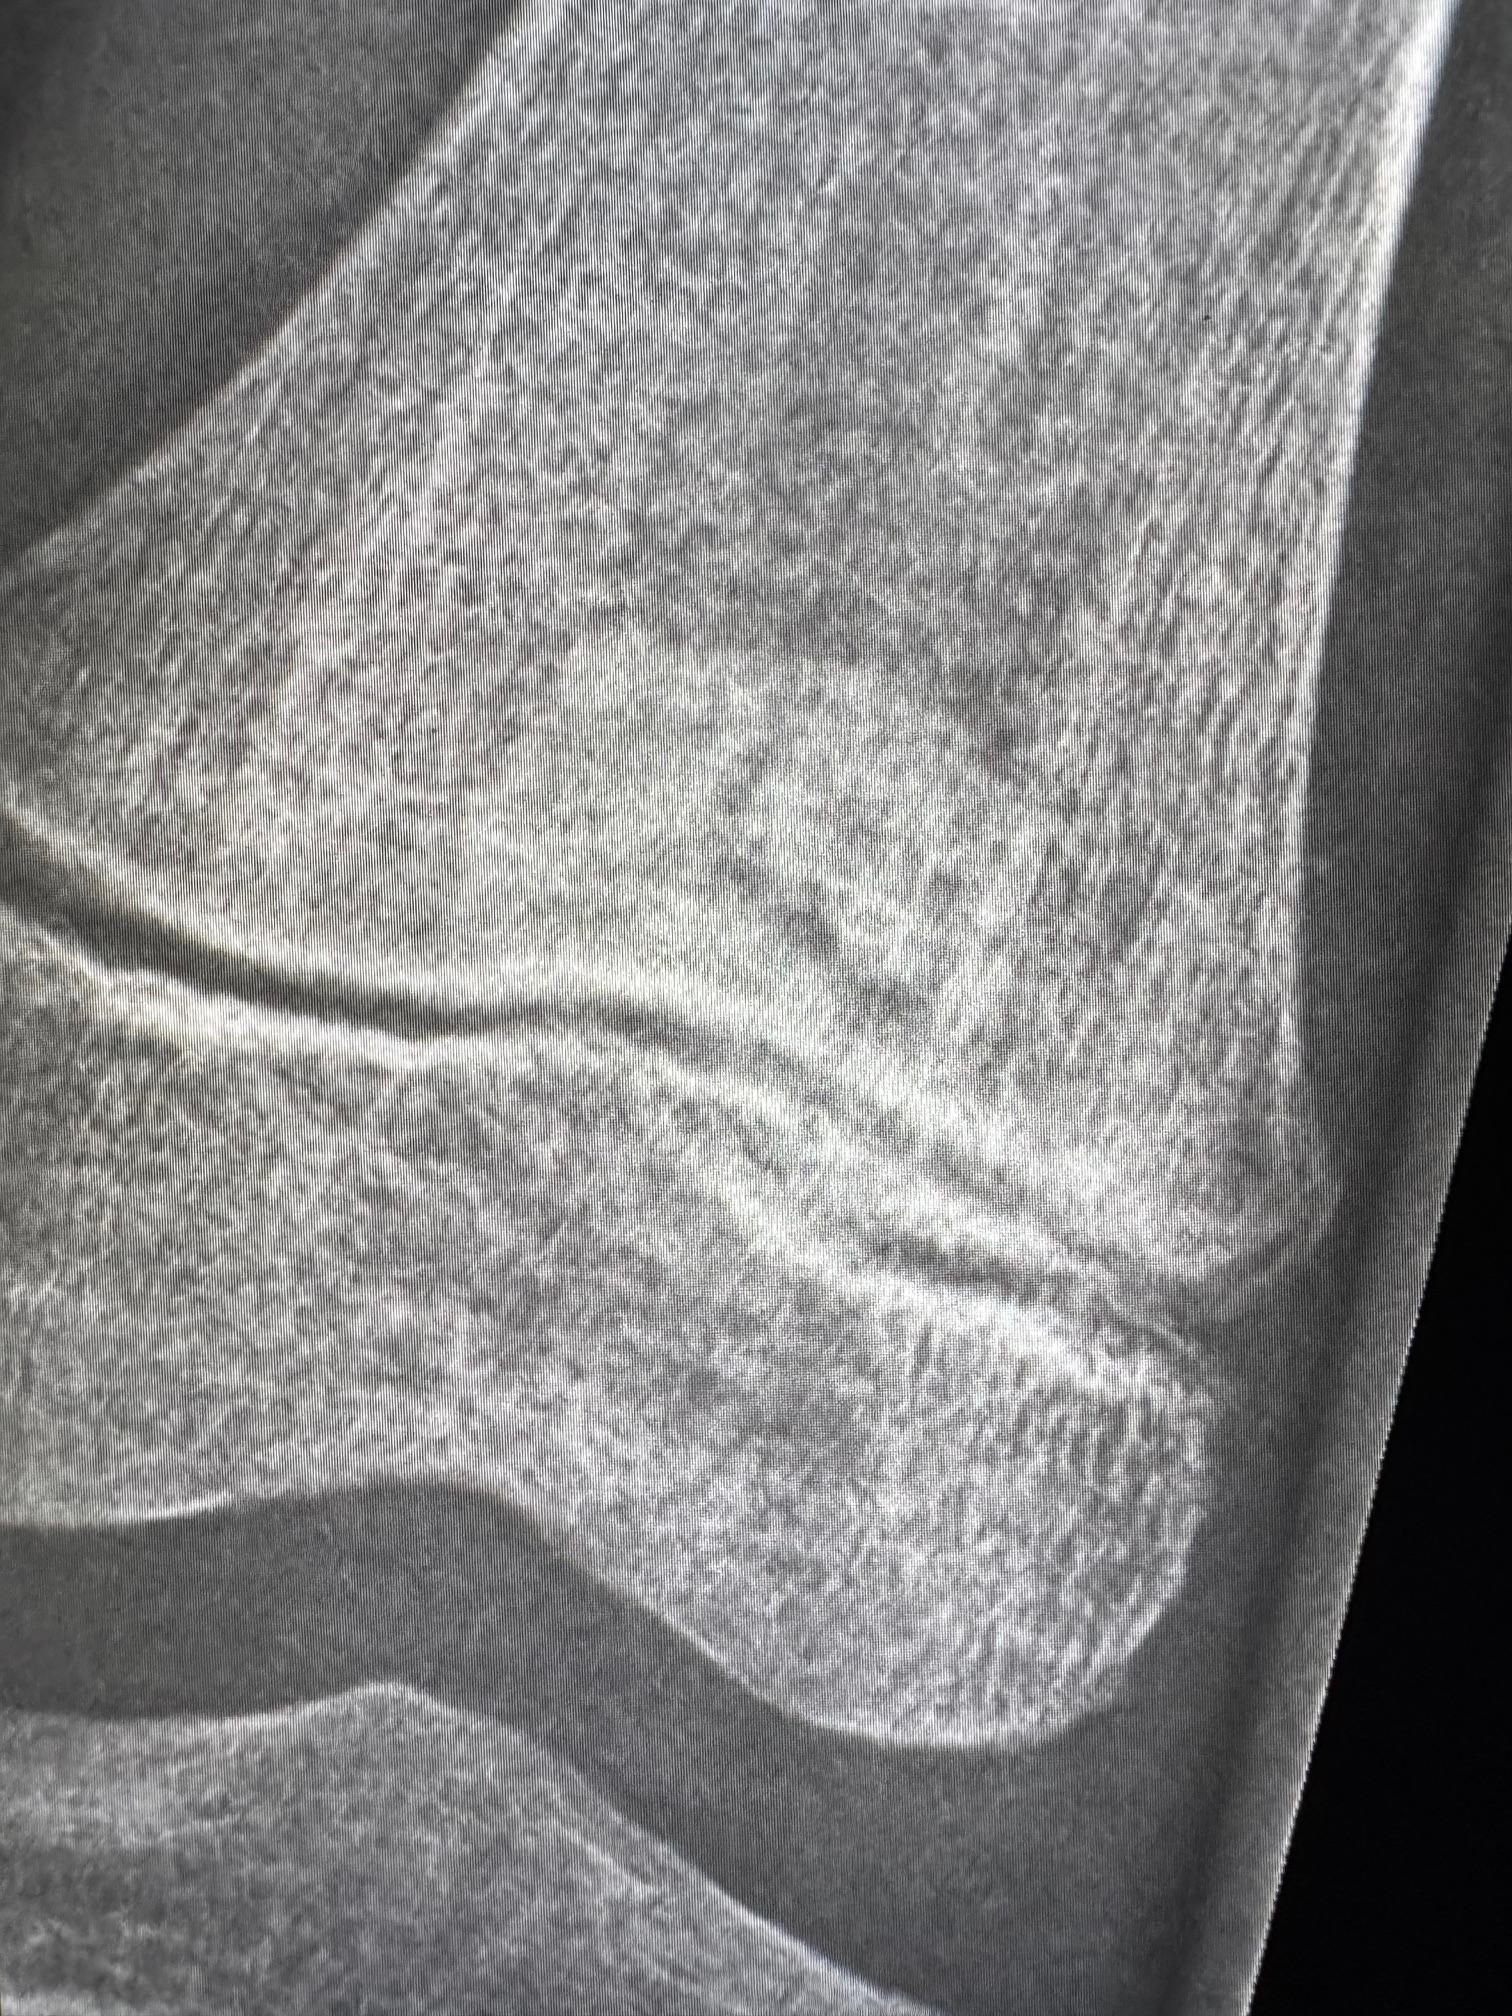

osteoid osteoma vs stress fracture of the distal fibula

Female, 13y, no trauma history. Osteoid osteoma vs. stress fracture of the distal fibula. I would like to hear your opinion. The radiographic study was obtained 45 days before the MRI and CT scan. Could this explain the absence of findings on the radiograph? Kind regards. André.